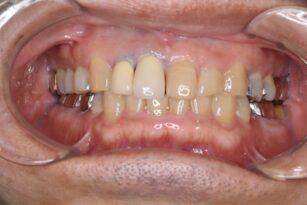

審美・補綴歯科

2025年12月22日

上の前歯の色が気になる 50代 女性 ジルコニアの症例